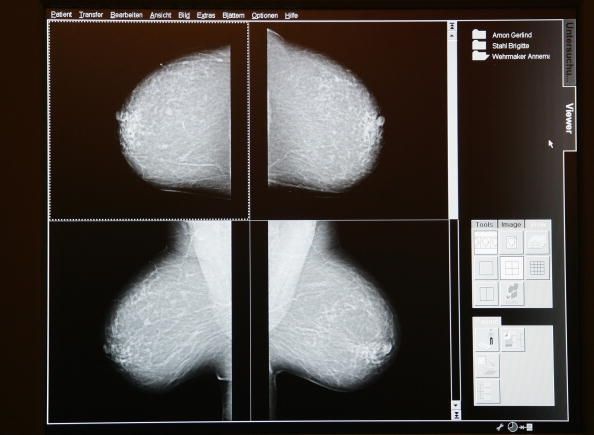

Las mujeres todavía comienzan a hacerse mamografías a los 40, a pesar de las nuevas directrices

A pesar del hecho de que algunas organizaciones de salud sugieren que las mujeres comienzan a hacerse mamografías de rutina a los 50 años, muchas mujeres todavía les comienzan a los 40 años El Grupo de Trabajo de Servicios Preventivos de Estados Unidos (USPSTF) cambió sus recomendaciones en 2009for cuando las mamografías de rutina para las mujeres sin factores de riesgo debe comenzar, pero todavía hay una cierta controversia.

Un estudio publicado en el American Journal of Preventive Medicine ha encontrado que no hubo ningún cambio perceptible en la edad en que las mujeres comenzaron a tener mamografías después de que el cambio en las recomendaciones. De hecho, la proporción de mujeres que comenzaron las mamografías a los 40 años había aumentado y fue mayor después del cambio. Este hallazgo se basa en una comparación de los datos de 2007 y 2008 a los datos de 2010 a 2012. Los datos, que se analizaron en 2014, fue recogido por las encuestas del Sistema de Vigilancia de Factores de Riesgo.

El USPSTF actualizó recientemente su recomendación, pero sólo para notar que las mujeres deben consultar con sus médicos a los 40 años en el momento adecuado para empezar las mamografías de rutina. El grupo de trabajo es un grupo voluntario de expertos en medicina y los informes al Congreso anualmente basada en la evidencia.

Las recomendaciones del USPSTF comenzaron un debate nacional en el año 2009 cuando se debe comenzar las mamografías de cribado. Aunque todos los cánceres de mama y de los grupos de defensa de la salud pública de acuerdo en que las mujeres deben hacerse mamografías para detectar el cáncer, no están de acuerdo en que las pruebas deben comenzar y con qué frecuencia las mujeres deben conseguirlos.

Por ejemplo, la Sociedad Americana del Cáncer recomienda que todas las mujeres tienen una mamografía anual a partir de los 40 años Sin embargo, hasta 1992, la sociedad recomienda que las mujeres comiencen a hacerse mamografías a los 35 años.

Hay una relación riesgo-beneficio de tener una mamografía de enrutamiento. Usted podría tener un falso positivo, donde la prueba muestra un tumor que no existe, lo que puede causar ansiedad y dar lugar a gastos de salud adicionales.